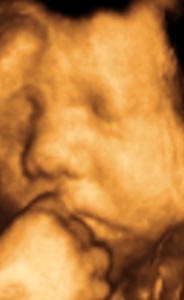

香港结构超声波照片

结构性超声波, 四维 香港, 四维结构性超声波 结构性超声波, 四维 结构性超声波, 四维 香港, 四维结构性超声波 结构性超声波, 四维 香港, 四维结构性超声波 结构性超声波, 四维 结构性超声波, 四维 结构性超声波, 四维 香港, 四维结构性超声波 结构性超声波, 四维 香港, 四维结构性超声波 结构性超声波, 四维 结构性超声波, 四维